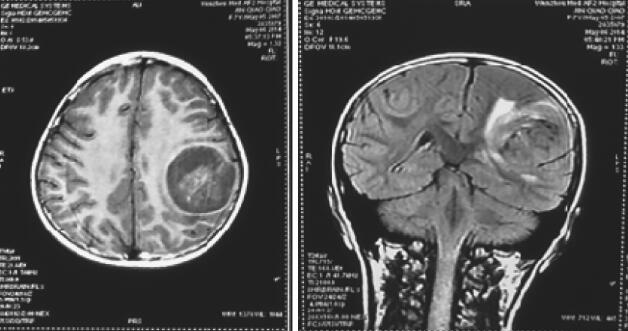

辅助检查:外院头颅MRI提示:左侧额顶叶肿瘤(图1)。

图1 外院头颅MRI(2014-5-8)提示左侧额顶叶肿瘤